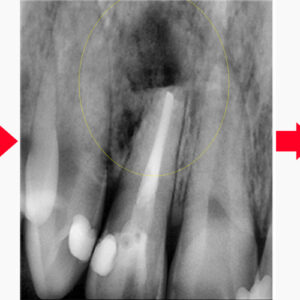

16. 울산치과 발치하기 전에 치료해보고

울산치과 발치하기 전에 치료해보고     안녕하세요. 모든 진료에 진심을 다하는 곳, 더플러스치과입니다. ​ 사람들이 병원들 중에서도 치과를 무서워하는 이유는 신경치.료라 해도 과언이 아닐 텐데요.   주변의 경험담이나 본인이 겪은 경우 더욱 이를 회피하게 됩니다.   특히 힘들게 진행했던 치료 후 염증이 재발하여 발치 가능성을 듣게 된다면 절망적일 수 있는데요. 더보기…